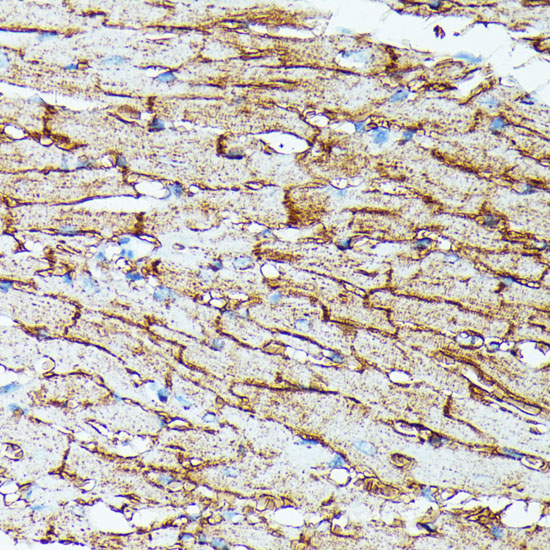

Immunohistochemistry of paraffin-embedded mouse heart using SLC14A1 at dilution of 1:100 (40x lens).